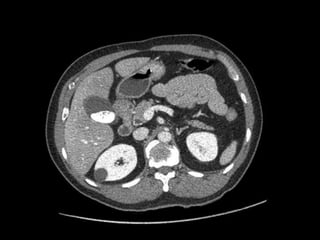

Colecistite Gangrenosa

Achados na TC:

Membranas intraluminais;

Hemorragia para o lúmen;

Parede irregular ou ausente;

Abscesso perivesicular;

Gás lúmen/parede.

Sensibilidade: 29,3%

Especificidade: 96%

Acurácia: 86,7%

Colecistite Gangrenosa Achados na TC: Membranas intraluminais; Hemorragia para o lúmen; Parede irregular ou ausente; Abscesso perivesicular; Gás lúmen/parede. Sensibilidade: 29,3% Especificidade: 96% Acurácia: 86,7%